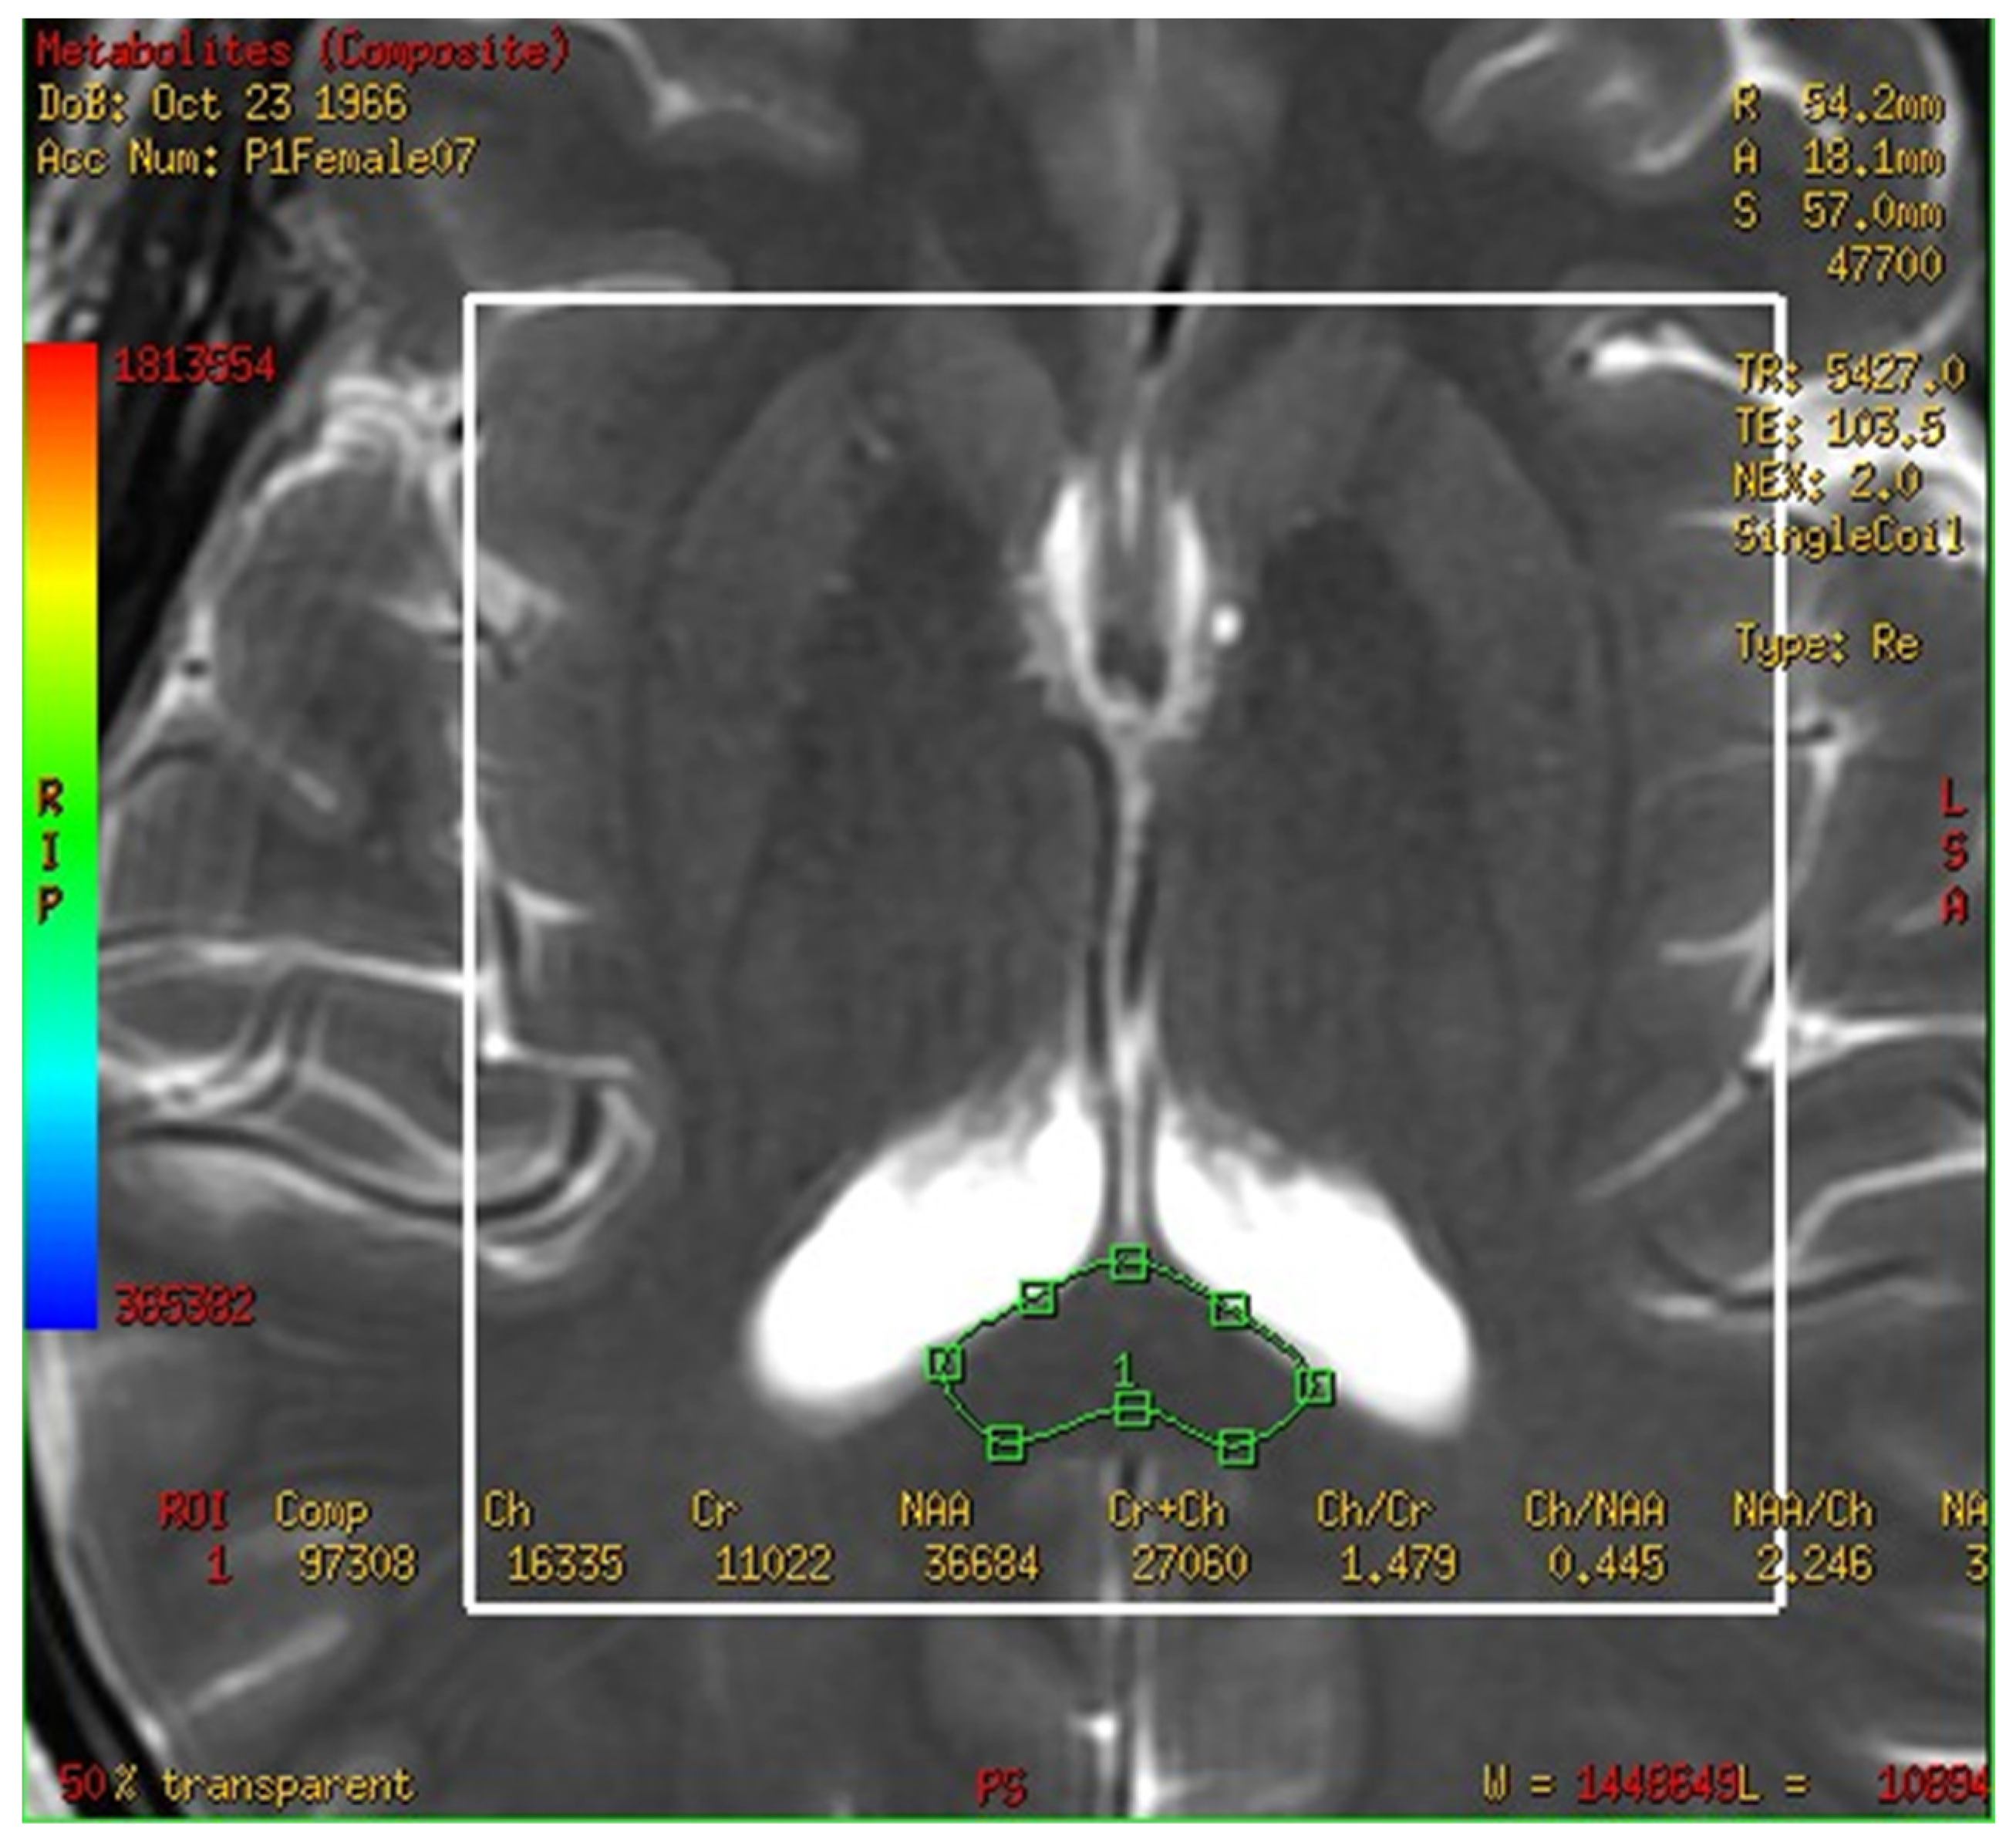

In this study, a medical 1.5 T MRI machine (GE Signa HDxt Medical Systems, Waukesha, WI, USA) and a standard head coil (Head Coil) in Camillians Saint Mary’s Hospital Luodong were used to receive signals from brain images of MRI T1 and T2 sequences, and 1H-MRS with 3D-CSI (echo time (TE) 144 ms, repetition time (TR) 1000 ms) for all participants. The range of chemical shift was set from 0 to 4 ppm, as this could include the signal of most metabolites in the brain, and the volume of each voxel was set at approximately 1–1.5 square centimeters. The measurements were performed as follows: First, brain images of T1 and T2 sequence with 3-Plane localization (sagittal, axial, and coronal planes) were obtained to locate the hippocampus and corpus callosum in the brain. Second, the three-dimensional space of the hippocampus and corpus callosum was manually marked and chosen on the image by a technician. Subsequently, the three-dimensional space of the hippocampus was divided into the total (bilateral), right, and left hippocampi. Third, the MRS with 3D-CSI was performed in the chosen location of the hippocampus (Figure 1) and corpus callosum (Figure 2). The signal intensities of choline (Cho), N-acetyl aspartate (NAA), creatine (Cr), and myo-inositol (MI) in the total (bilateral), right, and left hippocampi and the corpus callosum were measured and recorded in arbitrary units and used for statistical analysis.

Figure 2.

Magnetic resonance spectroscopy with three-dimensional chemical shift images in the chosen location of the bilateral corpus callosum (green markup). The signal intensities of metabolites were measured and recorded.